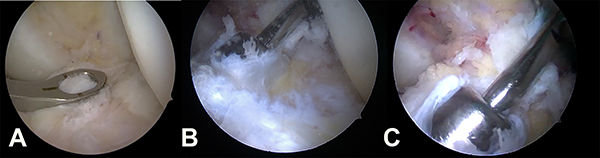

A continuación, la reconstrucción del LCA fue practicada con técnica transportal medial (anatómica), permitiendo cubrir mejor la huella femoral. Se usó un punzón de microfracturas para marcar el centro de la huella en 90° de flexión; se procedió a apoyar en ese punto la punta espada, se flexionó la rodilla a 120° y se pasó la misma, luego se fresó 9 mm (fig. 1) y posteriormente se realizó el túnel tibial con guía a 55°, utilizando una fresa 8 y luego usando dilatador de 9 mm para compactar el hueso esponjoso (fig. 2).

Figura 1:Visión artroscópica de rodilla izquierda. A) Cartílagos y menisco interno sanos. B) Cartílagos y menisco externo sanos. C) Lesión completa del LCA. D) Túnel femoral realizado por portal AM.

Es importante destacar que el IB en ningún momento compite con el injerto de reconstrucción del LCA. En flexión, el FiberTape® se relaja. Por el contrario, cuando la rodilla se extiende se puede observar como el FiberTape® se tensa para evitar sobreconstreñir la rodilla o competir con la integración del injerto, y así cumplir su función de cinturón de seguridad (fig. 6).

Figura 6: A-B) Visualización artroscópica en 90° de flexión. Plástica del LCA con aloinjerto de tibial anterior, InternalBracetm más laxo. C-D) Visualización en extensión, InternalBracetm con buena tensión.

Luego de la fijación tibial se realizó visualización final de la reconstrucción del LCA y refuerzo con InternalBracetm (fig. 7).

Figura 7: Visualización final de la reconstrucción del LCA con aumentación InternalBracetm.